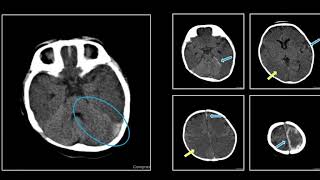

Imaging Of Traumatic Brain Injury Epidural And...

Subdural Hemorrhage Interesting Radiology Cases

Brain Ct Mystery Can You Spot The Subdural...